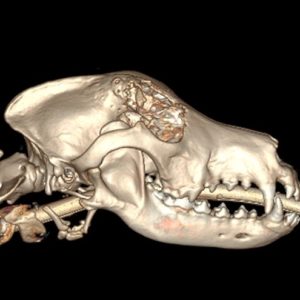

• Head/ Skull Tumours- nasal and oral

Diagnostic Imaging plays an important part in showing us the size of a tumour, where it is and what other areas are involved.

Generally your pet will need at least one form of diagnostic imaging before a treatment plan is discussed.  At VSA we are able to offer Ultrasounds, X-rays, CT Scans and MRIs.

The most important thing we can do with any VSA Cancer Care patient is to work up a treatment plan that individually suits them and their family.  To do this we need to have an accurate diagnosis and an understanding of the degree in which the cancer has progressed or spread.

This is where our Imaging Department comes in. During your pet’s initial consult with one of our specialist surgeons or internal medicine specialists they may recommend the need to do further imaging such as an ultrasound, CT or MRI even if you pet has already had radiographs or an ultrasound at your general practice clinic.

This form of imaging is known as “staging”. Staging helps us determine the size of a tumour and whether the cancer has spread to other parts of the body, known as metastases.

Our radiologists are experts in the interpretation of all imaging modalities, from X-rays, ultrasounds, CT and MRI. They are also able to safely obtain tissue samples by FNA and biopsies with either ultrasound or CT guidance.